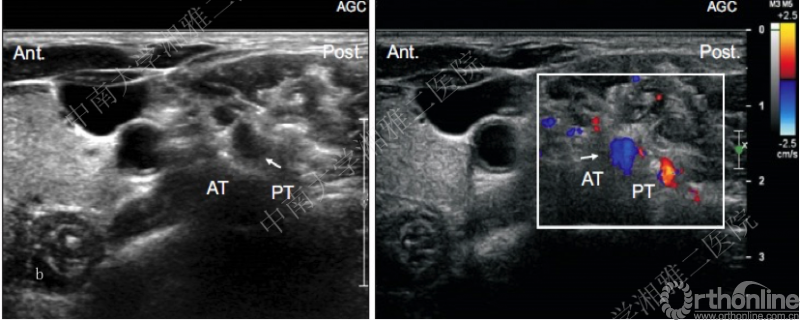

SCNRB超声引导技术

鉴于X线、CT引导在SCNRB技术中的应用局限,近年来,有学者倡导在超声引导下进行SCNRB。在超声对椎间孔周围血管扫描观察研究中[18]显示无论是在C5节段(图a),还是在C6节段(图b),实时多普勒模式下可以清晰辨别椎间孔神经根周围的细小动脉血管,按照表1的统计结果我们可以更好的发现,在传统的穿刺路径上越是颈椎低节段穿刺,穿刺针误入小动脉血管的风险越高。因此超声引导SCNRB可能具有的优势在于:1.无辐射 2.有效避免小动脉血管损伤[19]。

图b